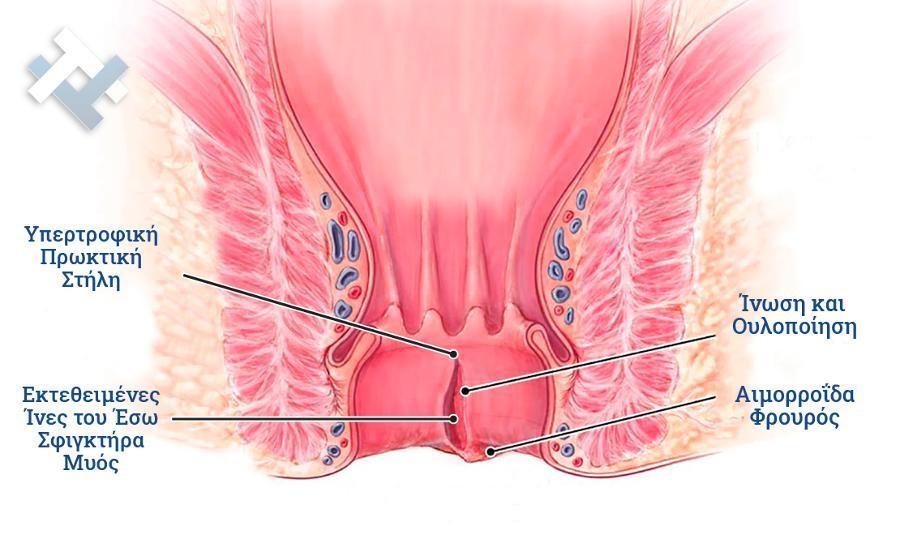

Ο Γενικός Χειρουργός Λιάγκος Γεώργιος MD PhD εκτελεί τις επεμβάσεις Λαπαροσκοπικά, Ενδοσκοπικά, Ανοιχτά Ελάχιστα Επεμβατικά και με Laser. Η θεραπεία εξατομικεύεται σε κάθε ασθενή ανάλογα με τις ανάγκες του. Αναλαμβάνει περιπτώσεις όπως κήλες και κοιλιοκήλες (αντιμετώπιση βουβωνοκήλης, αντιμετώπιση ομφαλοκήλης, θεραπεία επιγαστρικής κήλης, κήλη των αθλητών (Σύνδρομο κοιλιακών προσαγωγών), αντιμετώπιση μετεγχειρητικής κήλης, θεραπεία Μηροκήλης), πέτρες στη χοληδόχο κύστη, λαπαροσκοπική χολοκυστεκτομή, αντιμετώπιση Κύστη Κόκκυγος με λέιζερ (laser), παθήσεις πρωκτού, χειρουργική laser σύγχρονων κυκλικών ινών (αιμορροΐδες αντιμετώπιση, θεραπεία αιμορροϊδων με laser (LHP), αφαίρεση αιμορροΐδων με υπερήχους (HALL-RAR), χωρίς Χειρουργείο με ελαστικούς δακτυλίους (Τεχνική BARON-RBL), θεραπεία ραγάδας πρωκτού (Ραγάδα δακτυλίου), θεραπεία περιεδρικού συριγγίου, θεραπεία περιεδρικού αποστήματος, κονδυλώματα πρωκτού Θεραπεία, δερματικό ράκος (Skin tag) εκτομή, αντιμετώπιση Kνησμού, καρκίνος πρωκτού θεραπεία), παθήσεις Δέρματος, χειρουργική με laser CO2, αφαίρεση μορφωμάτων δέρματος - βιοψίες, αφαίρεση ελιάς (Σπίλου), σμηγματογόνος κύστης θεραπεία, αφαίρεση λιπώματος, είσφρυση όνυχος χειρουργείο, καρκίνος δέρματος θεραπεία, οξεία σκωληκοειδίτιδα, παθήσεις Λεπτού και Παχέος Εντέρου, ειλεός λεπτού εντέρου, εκκολπωμάτωση (Εκκολπωματίτιδα) σιγμοειδούς, καρκίνος παχέος εντέου, κολοστομίες, port χημειοθεραπείας κ.α. εξυπηρετώντας Παγκράτι και γύρω περιοχές.